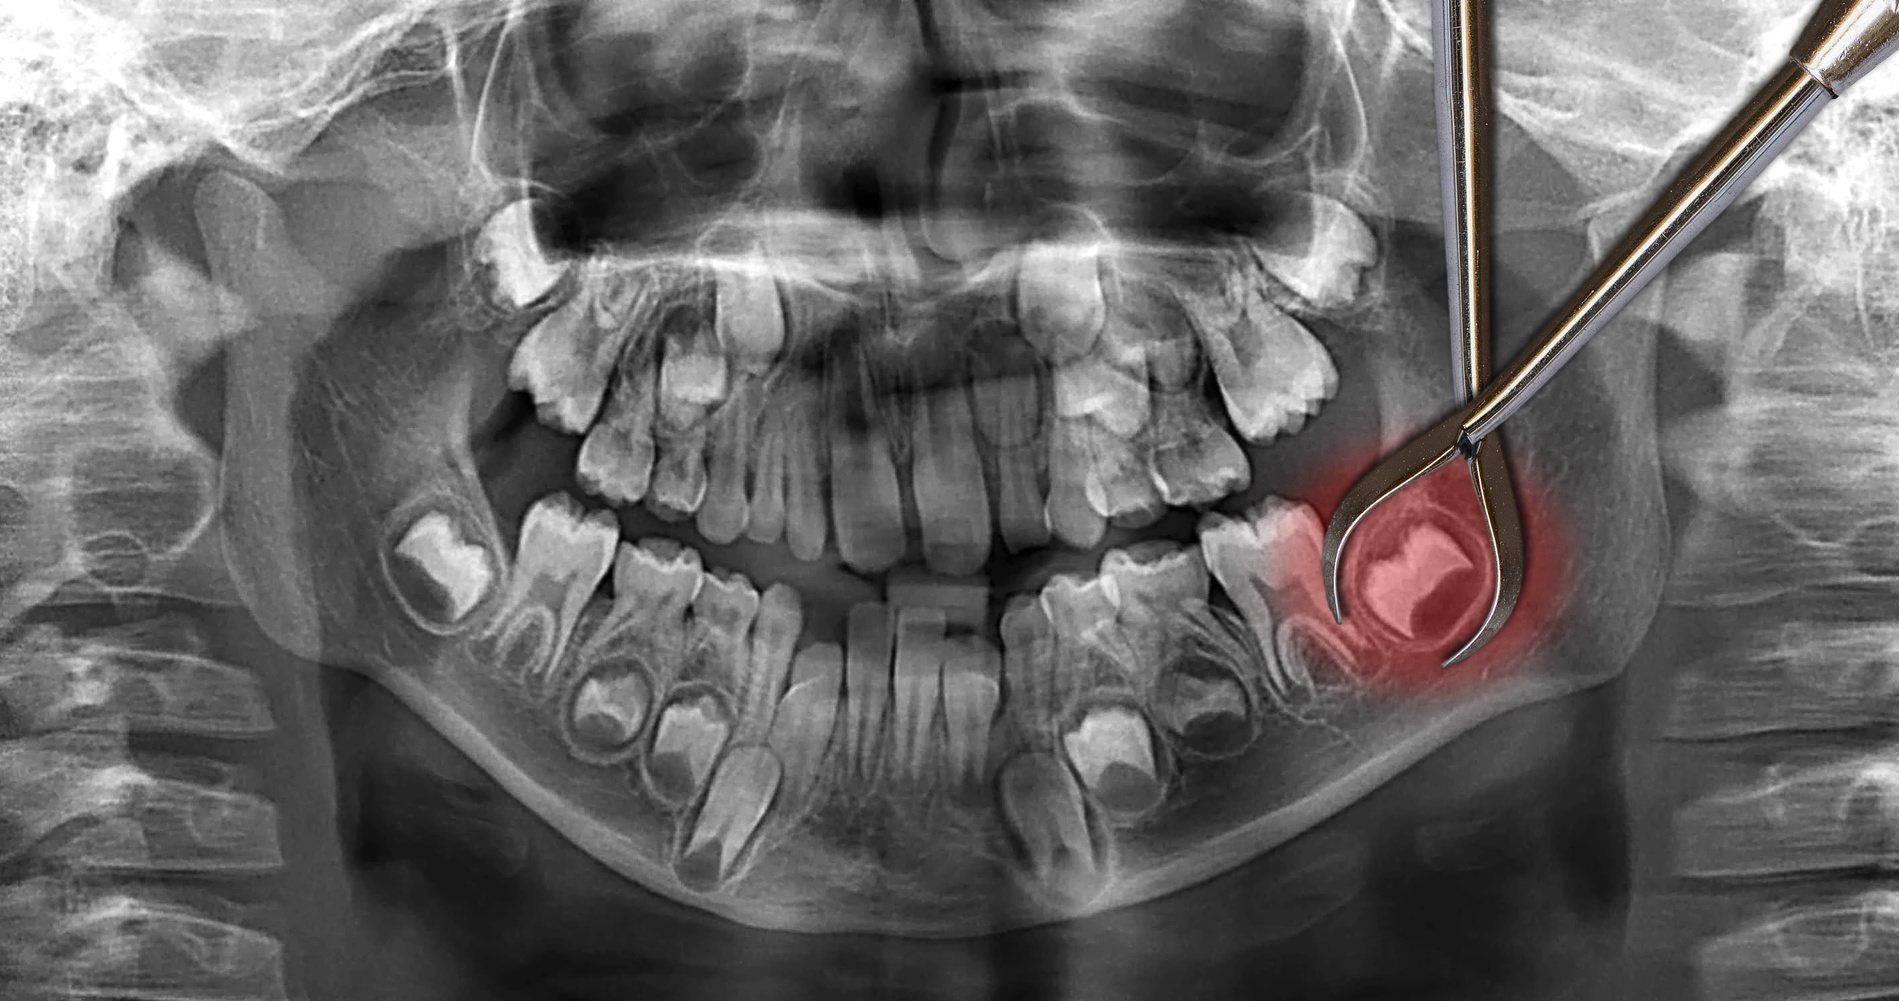

Clinical Procedure

If the wisdom teeth are impacted and embedded in the bone, the oral surgeon will put an incision into the gums and remove the tooth or teeth in sections in order to minimise the amount of bone being removed. Some pain and swelling may occur, but it will normally go away after a few days; however, you should call your dentist or oral surgeon if you have prolonged or severe pain, swelling, bleeding or fever.

Impacted wisdom teeth are our specialty. We use 3D imaging to see exactly where your teeth are positioned and plan the safest extraction approach. Even deeply impacted teeth can usually be removed in 30-45 minutes. Early removal prevents future problems like infection, cysts, and damage to other teeth.